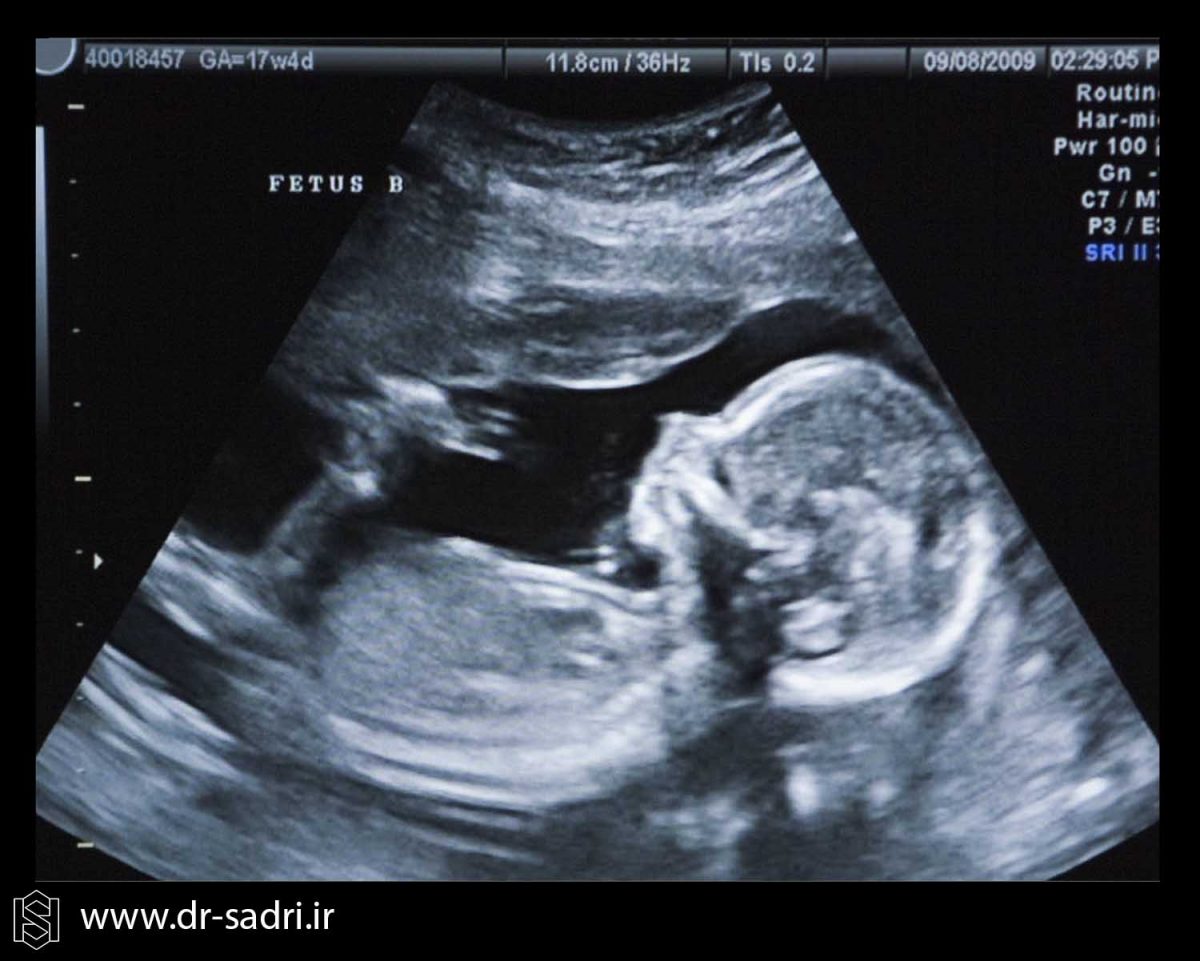

عکس جنین مبتلا به سندروم داون

[…] NT پیشنهاد می دهد. این سونوگرافی برای غربالگری سندرم داون انجام میشود و دانستن اینکه چقدر از بارداریتان می گذرد […]

[…] سندرم داون را می توان در سونوگرافی هفته ۱۲ ام به طور دقیق شناسایی […]